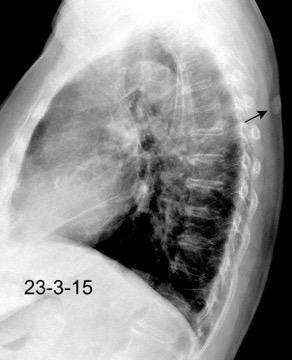

Nódulo en língula.

Cirugía de Ca .de mama hace 23 añosedema de brazo y ganglio en axila. ¡Metástasis!.